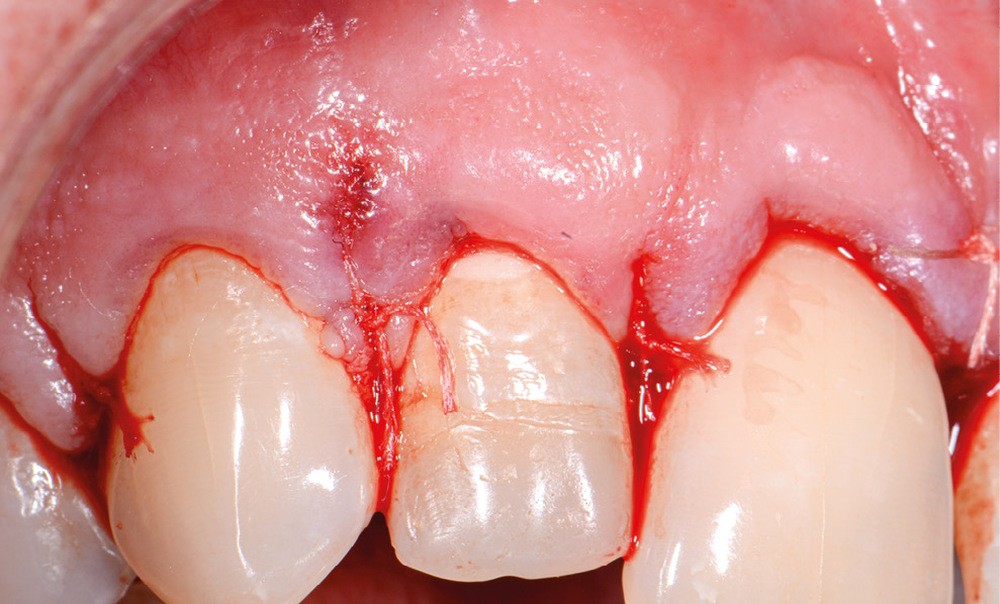

10. réalisation d’un lambeau, en commençant par l’incision intra-sulculaire à l’aide d’une lame de bistouri n° 15C, s’étendant de deux dents en mésial et distal de la dent perforée (de manière à avoir une laxité suffisante pour exposer aisément la zone de perforation – accès visuel et instrumental) ;

11. décollement du lambeau (décolleur de Molt) : décoller les papilles dans un premier temps, puis la gencive kératinisée en pleine épaisseur de sorte à éviter de déchirer le lambeau ;

18. rinçage du lambeau et remise en place du lambeau de pleine épaisseur ;

19. sutures de préférence à l’aide de fil non résorbable, diamètre fin (Ex 5/0) au niveau des papilles décollées (points simples ou matelassiers verticaux) ;

20. conseils postopératoires, prescription antalgique (palier I), bain de bouche, brosse à dents chirurgicale.